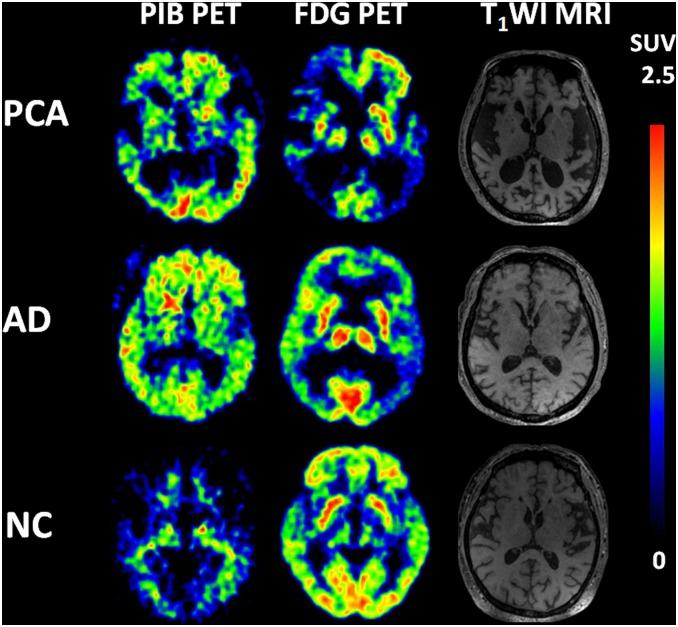

Posterior cortical atrophy (PCA) is a clinicoradiologic neurodegenerative syndrome characterized by predominant impairment of higher visual functions. Neuroimaging and neuropathological studies show that PCA is probably an atypical presentation of Alzheimer's disease. However, in China PCA has rarely been studied and remains largely unknown. Our study therefore aimed to analyze the clinical manifestations and patterns of cerebral atrophy, amyloid beta deposition and regional glucose metabolism in Chinese PCA patients, comparing them directly with those of typical Alzheimer's disease (TAD). Seven PCA patients, 6 TAD patients and 5 controls underwent neuropsychological assessment, MRI scan, 11C-PIB PET scan and 18F-FDG PET scan. Cerebral atrophy including ventricular enlargement, posterior atrophy and medial temporal lobe atrophy were evaluated with MRI. The uptake of 11C-PIB was quantified at the voxel level using the standardized uptake value ratio. Comparisons of regional cerebral glucose metabolism were calculated with statistical parametric mapping. PCA patients showed significant impairment on visuospatial function in neuropsychological assessment. And PCA patients showed more severe posterior atrophy and less severe left medial temporal lobe atrophy compared with TAD patients. The data from 11C-PIB PET scanning showed that amyloid beta deposition in PCA was comparable to TAD. Moreover, in PCA the results from 18F-FDG PET scanning revealed significant hypometabolism in the temporoparietooccipital region and identified specific hypometabolism in the right occipital lobe, compared with TAD. Our study thus provides a preliminary view of PCA in Chinese patients. A further study with a larger number of subjects would be recommended to confirm these findings.

后部皮质萎缩(PCA)是一种临床放射学神经退行性综合征,其特征是高级视觉功能主要受损。神经影像学和神经病理学研究表明,PCA可能是阿尔茨海默病的非典型表现。然而,在中国,PCA很少被研究,在很大程度上仍然不为人知。因此,我们的研究旨在分析中国PCA患者的临床表现、脑萎缩模式、淀粉样β蛋白沉积和区域葡萄糖代谢情况,并将其与典型阿尔茨海默病(TAD)患者进行直接比较。7例PCA患者、6例TAD患者和5名对照者接受了神经心理学评估、MRI扫描、11C-PIB PET扫描和18F-FDG PET扫描。通过MRI评估包括脑室扩大、后部萎缩和内侧颞叶萎缩在内的脑萎缩情况。使用标准化摄取值比率在体素水平对11C-PIB的摄取进行定量。采用统计参数映射计算区域脑葡萄糖代谢的比较情况。PCA患者在神经心理学评估中显示出明显的视觉空间功能受损。与TAD患者相比,PCA患者表现出更严重的后部萎缩和较轻的左侧内侧颞叶萎缩。11C-PIB PET扫描数据显示,PCA中的淀粉样β蛋白沉积与TAD相当。此外,与TAD相比,PCA的18F-FDG PET扫描结果显示颞顶枕叶区域存在明显的代谢减低,并在右侧枕叶发现了特定的代谢减低。因此,我们的研究提供了中国PCA患者的初步情况。建议进行进一步的研究,纳入更多受试者以证实这些发现。